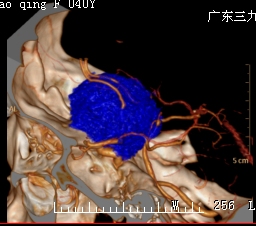

王女士,40岁, 5年前开始出现右眼视物模糊,1年前开始出现左眼视物模糊,为求治疗,来我院就诊。病人由神经外一科接诊,完善相关术前检查,结果示:肿瘤组织包绕神经、动脉,考虑到手术的风险性,科室组织专家反复进行术前讨论,拿出最佳的手术方案,由神经外一科主任张良主刀完成。

行全麻下右侧扩大翼点入路鞍结节脑膜瘤切除术。术中见右侧视神经、颈内动脉被肿瘤包绕,肿瘤血供丰富,肿瘤起源于鞍结节及鞍隔。术中全切肿瘤,神经、血管、垂体柄完好。术后病理示:鞍区脑膜瘤,部分为过渡细胞型,部分为血管瘤型脑膜瘤,WHO I级。术后左侧视力同术前,右侧视力较术前稍差。 经系统的治疗后康复出院。

广东三九脑科医院神经外一科张良主任介绍:鞍结节脑膜瘤的手术入路应根据肿瘤的大小及其生长部位等进行选择。常见的手术入路包括单侧额底入路、双侧额下入路、翼点入路、双额纵裂入路等,每种手术路径各有其优缺点。国外专家认为,肿瘤直径较小时采用单侧额底入路效果较好,但易损伤嗅神经及额叶;对于巨大型肿瘤易采用双额纵裂入路;对于居中线一侧向鞍后生长的肿瘤易采用翼点人路,因其不易由于牵拉而损伤嗅神经及额叶。但无论选择何种手术路径,都应先充分释放脑脊液,以降低颅内压和分开或抬起额叶,从而扩大手术视野。本例患者肿瘤起源于鞍结节,肿瘤从前颅窝底一直生长到上斜坡,所以选择翼点入路,手术中主要从第一间隙操作,全切肿瘤,垂体柄保留良好,没有尿崩。手术入路选择除了考虑肿瘤的情况外,还要考虑手术者对入路的熟悉情况。

血管瘤型血供丰富,控制术中出血尤其重要。术前通过影像学了解肿瘤的供血情况,术中优先对肿瘤基底部(鞍结节处)进行处理,阻断其血供,从而减少术中出血,鞍隔处不要急于处理,以免损伤垂体柄。之后再对肿瘤进行分块切除,应先从无重要结构的中心部位进行分块切除。剥离小块肿瘤时应谨慎,避免拉断其周围的神经、血管等,还应尽量减少对视神经的牵拉,切勿损伤视器的血供,同时手术应保持在蛛网膜下腔内操作,尽量避免直接损伤视神经。